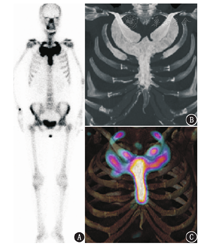

骨显像后1周,患者在局部麻醉下行CT引导的胸锁关节经皮穿刺骨活组织检查。光学显微镜下见大量异型细胞,核深染畸形,呈巢团状及筛孔状,病理结果提示为转移性腺癌。随后患者接受了上胸部局部外照射及唑来膦酸盐治疗。治疗后7个月复查骨显像,表现与治疗前大致相似,只是胸骨浓聚区弥散到胸骨全部;同机CT显示两侧锁骨、胸骨、第1、2肋骨呈弥漫性毛玻璃样改变,但两侧胸骨和锁骨关节面仍然光整(图2)。碱性磷酸酶及血红细胞沉降率均恢复到正常水平。

核素骨显像是检查SAPHO综合征的灵敏方法,图像上胸锁关节区的对称性浓聚呈典型的"牛头"征,颇具特征性[2,3,4]。SPECT/CT可显示滑膜炎导致的跨关节侵蚀、软骨剥脱及软骨下骨炎等病理改变。原发性或继发性骨肿瘤极少侵蚀关节软骨,不会形成跨关节破坏。本例有皮肤病史、血红细胞沉降率升高,及典型的"牛头"征,类似SAPHO综合征骨显像表现;但累及关节的关节面完整,关节软骨及软骨下骨未见侵蚀破坏和硬化,未见关节间隙肿胀,亦无骨膜反应导致的骨肥厚,不符合关节炎的典型影像表现。本病例表明胸锁关节区"牛头"状浓聚不是SAPHO综合征的独有表现,SPECT/CT有助于诊断和鉴别诊断。